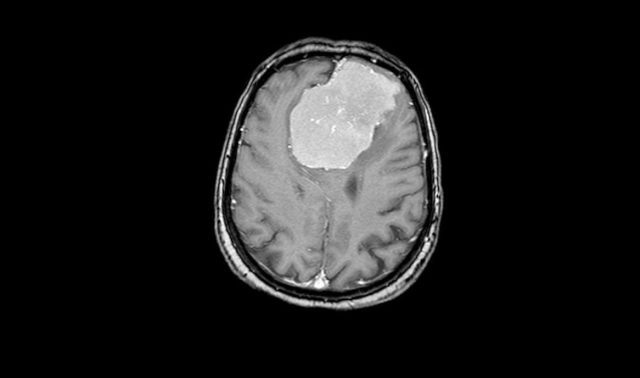

Фото предоставлено пресс-службой Минздрава Воронежской области

Женщину привезли в больницу с подозрением на инсульт. У неё ослабела правая рука. Также пациентке было тяжело говорить. Компьютерная томография показала, что инсульта нет. Однако результаты обследования оказались не менее тревожны. У пенсионерки нашли в обеих лобных долях мозга опухоль размером 6х7х8 см.

– Подобные новообразования так или иначе затрагивают важные участки мозга – кровеносные сосуды и зоны, отвечающие за речь и движение, – объясняют суть проблемы специалисты. – Дополнительное исследование с контрастом показало, что опухоль окутывала магистральные сосуды Велизиевого круга – переднюю мозговую артерию, а также прорастала в переднюю треть сагиттального синуса (один из наиболее крупных венозных коллекторов головного мозга) и закрывала его.